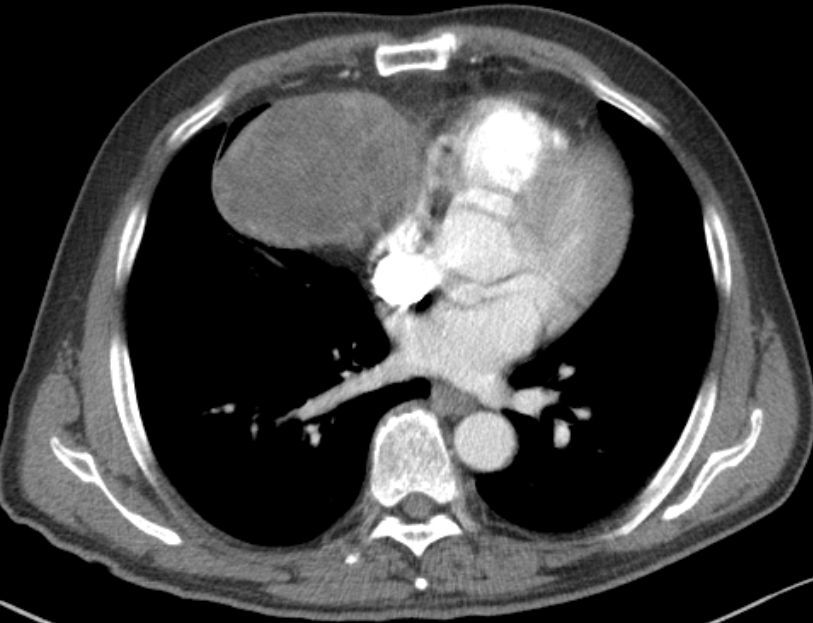

患者,女性,73岁,咳嗽,咳痰10余天,在当地医院行平扫诊断为纵膈肿瘤

左胸腔巨大肿瘤,左肺完全肺不张,纵隔右移!